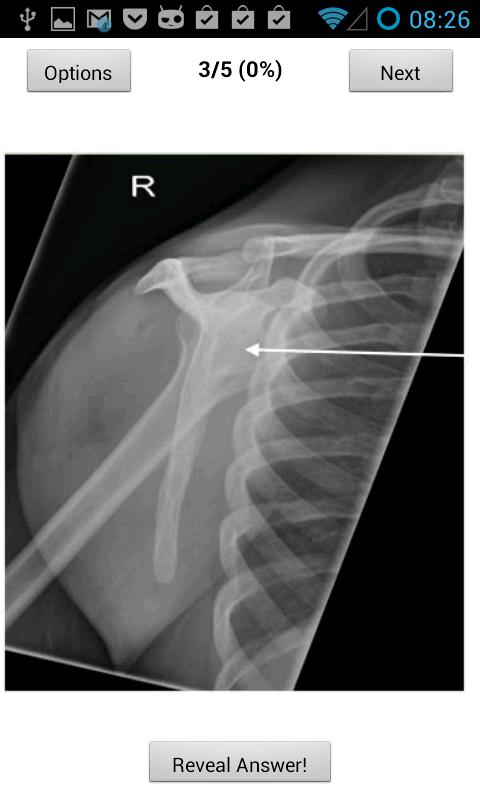

このアプリは、FRCRパート1の解剖学試験を実施している放射線科学候補を支援します。 60の無料試験スタイルの質問が含まれており、それぞれに1つのラベル(2013年の質問に従って)があり、さらに240の質問を購入するオプション***限られた時間の£0.50のみ***